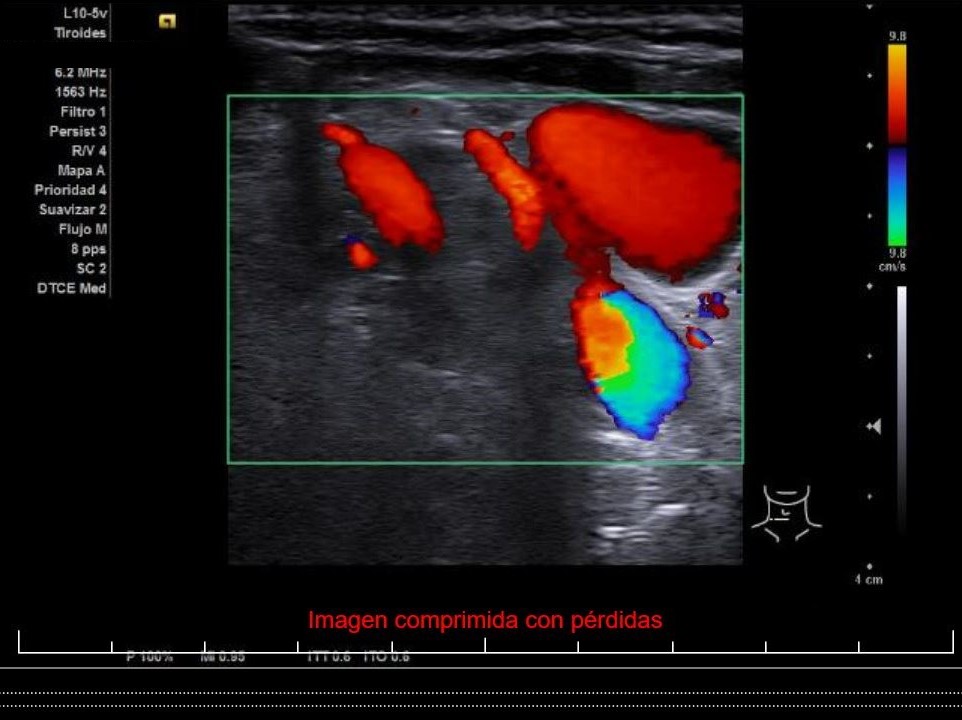

Se aprecia un tiroides de características ecográficas compatibles con tiroiditis, sin cambios respecto a ecografía previa, al igual que la grasa peritiroidea derecha, pero de manera incidental se observa un aumento del calibre fusiforme de la yugular externa derecha con respecto a la izquierda, con flujo vascular reducido.

Flebectasia yugular derecha.

La flebectasia yugular es la dilatación fusiforme o sacular de la vena, de etiología desconocida, diagnosticada habitualmente en la infancia, rara en adultos, secundaria a la delgadez de las paredes del vaso y que se hace evidente en situaciones en las que aumenta la presión dentro del mismo. Habitualmente se presenta como una masa blanda e indolora en el cuello, en ocasiones pulsátil y que varía de tamaño con las maniobras de Valsalva. De mayor a menor frecuencia se encuentra en la yugular interna, la externa y la anterior. El tratamiento de elección es el conservador.